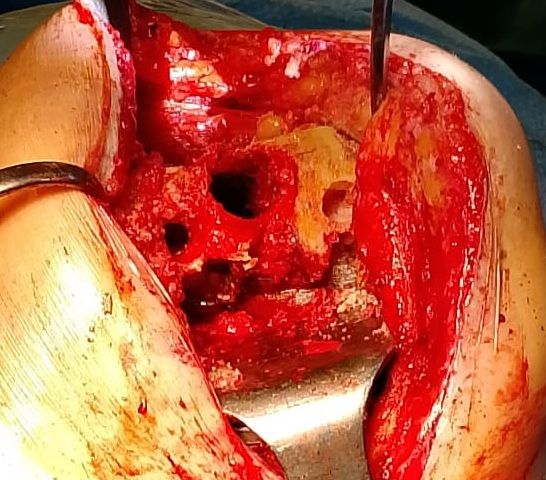

Da quando ha preso servizio presso l’Ospedale del Delta si è sempre occupato della chirurgia protesica del ginocchio sia monocompartimentale che totale acquisendo esperienza anche sulle tecniche basate sulla navigazione assistita che sull’impianto di protesi custom-made. Di routine esegue interventi di chirurgia artroscopica per il trattamento delle patologie meniscali e cartilaginee e di ricostruzione del legamento crociato anteriore mediante varie tecniche